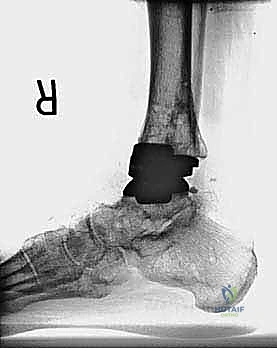

مراجعة مفصل الكاحل الصناعي هي إجراء جراحي ضروري لمعالجة المشاكل التي قد تنشأ بعد الجراحة الأولية، مثل كسور الكعبين أو عدم استقرار المفصل. يتضمن العلاج التشخيص الدقيق عبر الأشعة السينية والتصوير المقطعي، يليه التدخل الجراحي لتثبيت الكسور واستعادة وظيفة الكاحل، مع التركيز على التعافي المبكر.

تُعد جراحة مراجعة مفصل الكاحل الصناعي (Revision Total Ankle Replacement) من الإجراءات الجراحية المتقدمة والبالغة الدقة في عالم جراحة العظام الحديثة. لا تقتصر هذه الجراحة على مجرد استبدال مفصل تالف بآخر جديد، بل هي عملية إنقاذ معقدة للغاية تهدف إلى معالجة المشاكل الميكانيكية والبيولوجية التي تنشأ بعد الجراحة الأولية. من أبرز هذه المشاكل: الفشل الميكانيكي للمفصل، تحلل العظام (Osteolysis)، أو حدوث كسور معقدة في الكعبين (Malleolar Fractures) المحيطة بالمفصل الصناعي. يتطلب هذا الإجراء تقييماً سريرياً وشعاعياً دقيقاً يشمل التصوير المقطعي ثلاثي الأبعاد والأشعة السينية، يليه تدخل جراحي دقيق لاستعادة التوازن الحيوي والميكانيكي للكاحل والحفاظ على الطرف من البتر أو الدمج.

- الأشعة السينية مع تحميل الوزن (Weight-bearing X-rays): لتقييم الزوايا الميكانيكية وتحديد مدى هبوط المفصل أو وجود كسور في الكعب.

كسور الكعبين (Malleolar Fractures) المصاحبة للمفصل الصناعي

من أعقد التحديات التي تواجه جراحي العظام هي حدوث كسور في الكعب الداخلي (Medial Malleolus) أو الخارجي (Lateral Malleolus) في وجود مفصل صناعي. تحدث هذه الكسور لعدة أسباب:

علاج هذه الكسور يتطلب مهارة فائقة من الدكتور محمد هطيف، حيث يتم استخدام تقنيات الجراحة الميكروسكوبية وتثبيت الكسور باستخدام صفائح معدنية دقيقة ومسامير (Locking Plates) دون المساس بثبات المفصل الصناعي، أو يتم دمج علاج الكسر ضمن عملية مراجعة المفصل الكلية إذا كان المفصل نفسه تالفاً.